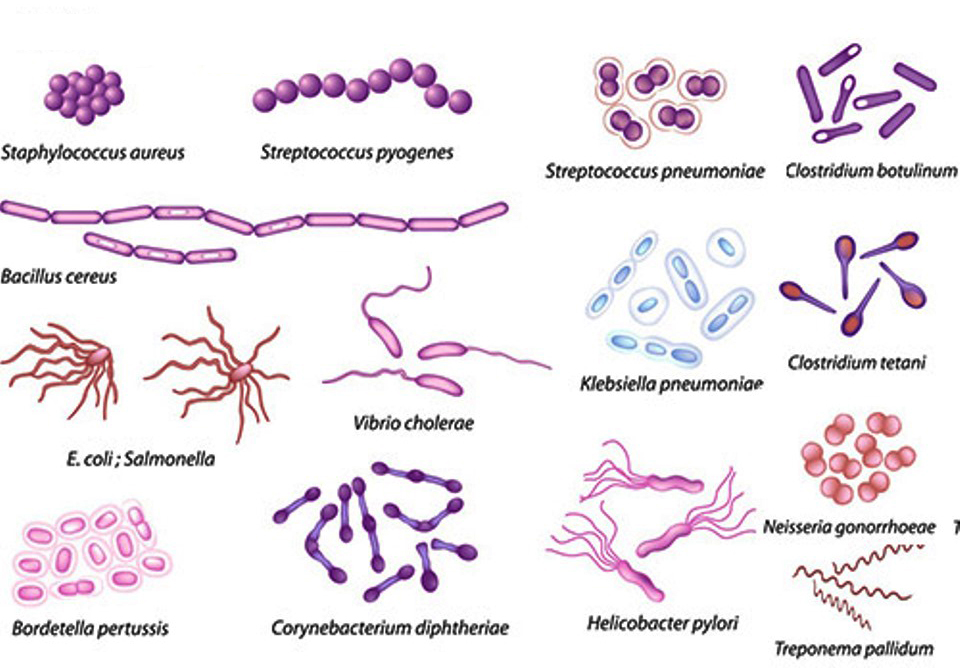

Ini Dia, 9 Bakteri Paling Berbahaya Bagi Manusia - MEDIAJABAR.com

Ini Dia, 9 Bakteri Paling Berbahaya Bagi Manusia - MEDIAJABAR.com

8 Bakteri Berbahaya dalam Makanan yang Sering Menyebabkan Keracunan

8 Bakteri Berbahaya dalam Makanan yang Sering Menyebabkan Keracunan

Mikrobiologi Bakteri | Pasundan Ekspres

Mikrobiologi Bakteri | Pasundan Ekspres

7 Bakteri dalam Makanan yang Membuat Anda Sakit

7 Bakteri dalam Makanan yang Membuat Anda Sakit

7 Bakteri pada Makanan yang Paling Banyak Sebabkan Penyakit Halaman all - Kompas.com

7 Bakteri pada Makanan yang Paling Banyak Sebabkan Penyakit Halaman all - Kompas.com